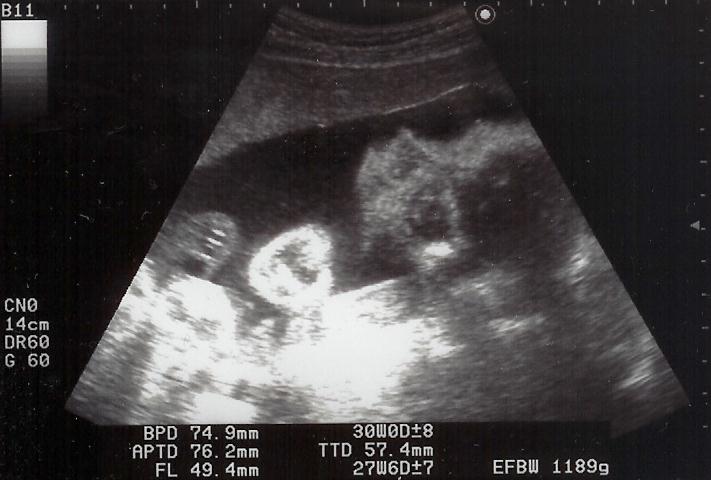

|  |  shigeru26週の健診です。shgieruは841gになりました。心音もしっかりしていて、元気・順調です。ママも今回は体重OK。でも、「塩分は控えめ」(高血圧気味)

と母子手帳に書かれてしまいました。